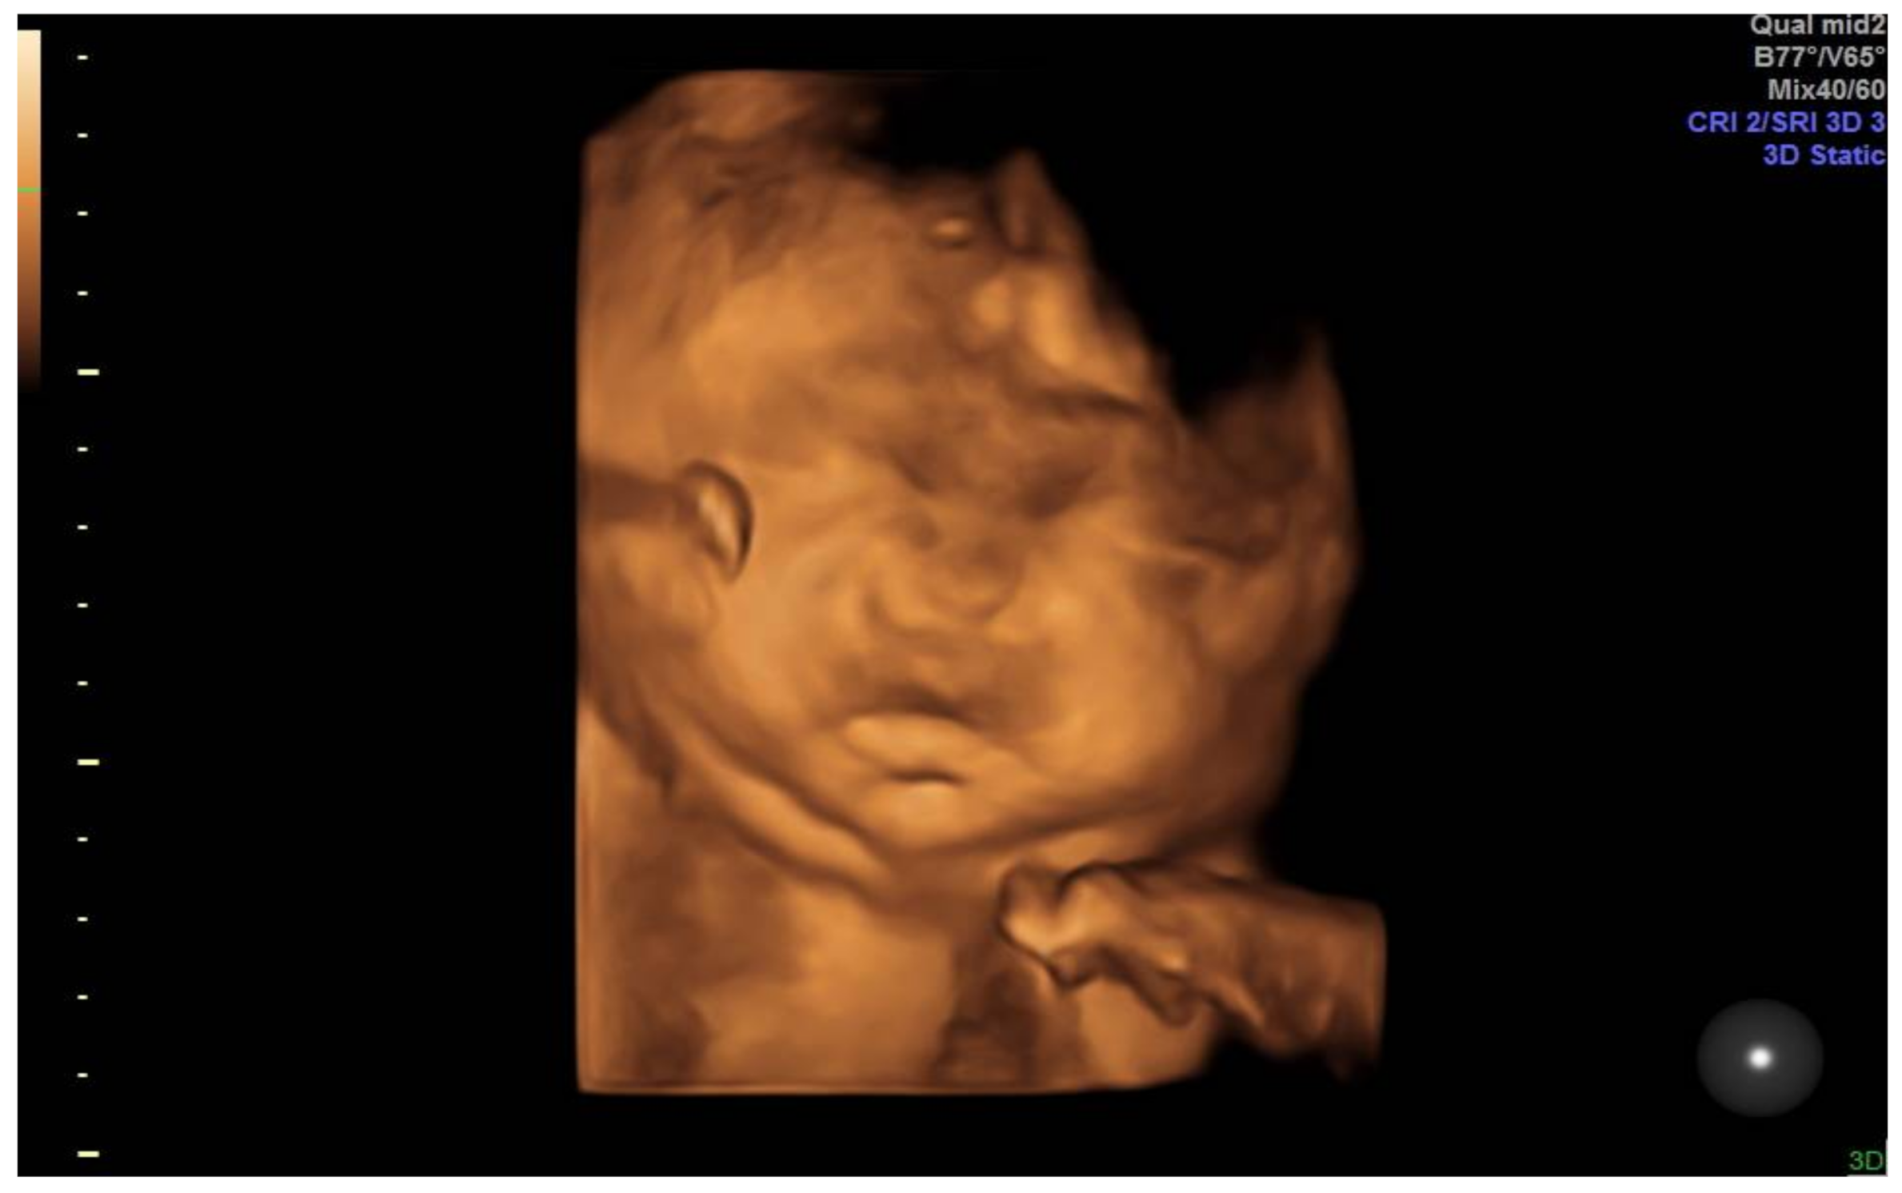

2. Case Presentation